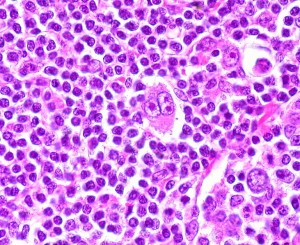

Recently, the FDA announced its approval, upon accelerated review, of a new drug, Adcetris (brentuximab) for patients with Hodgkin’s lymphoma that has relapsed after bone marrow transplant and for some patients with T-cell anaplastic large cell lymphoma (ALCL).

This interests me for a lot of reasons, among them that I used to work in the field of lymphoma immunology and spent some time in my life studying molecules like CD30, the protein to which the new antibody binds.

First, a mini-primer on the disease and numbers of patients involved: Read more »